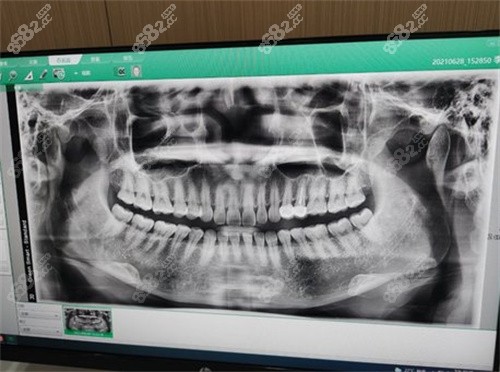

因为一直爱吃甜食,之前坏了颗牙也打算补一下, 亲戚说他们家是口腔的合作单位,技术上没得说,价位也不贵还不用排队,地段比较好,环境整洁舒适,而且全景的牙片看问题很明显,也给出了相应的方案,补完牙到现在感觉还不错!